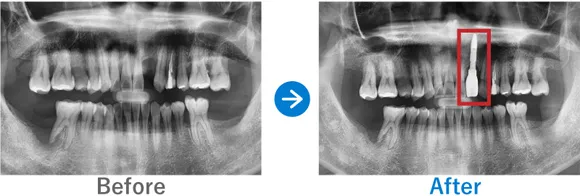

Case9

約30年間ぐらぐらしていた前歯をインプラントに。即時に仮歯が入り仕上がりにも納得

右上前歯のぐらつき

インプラント1本:右上1

347,000円(内訳:抜歯即時埋入、インプラント1本(ノーベル)、仮歯、保証5年)

来院の背景

19歳のときに転んだはずみで前歯がぐらつくようになり、これまで他院での治療でなんとか維持してきましたが、ここ最近で急にぐらぐらするようになってきたそうです。ご自身の感覚では歯の根元がダメになっている気がするので、早くなんとかしてほしいと来院されました。

治療結果

前歯がダメージを受けてから30年近く経っているため、骨吸収が進んで歯が長くなっている状態でした。一方で、歯の根っこの先には異常がないことを確認できたため、前歯ということもあり早めに治療をスタート。抜歯後にすぐ仮歯を入れる方法で治療を進めました。

骨吸収が進んでいたため歯は長めになりましたが、事前に説明していたこともありご納得いただける結果となりました。